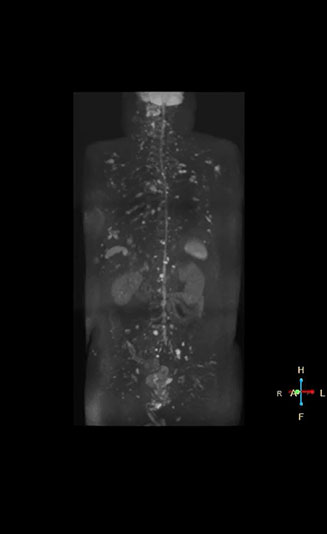

“When we limited the scan coverage to the area from neck to femur, we could fit more clinical information in approximately the same scan time. So, we added coronal mDIXON, sagittal T1-weighted, and sagittal STIR sequences to our examination, instead of performing only axial DWIBS and coronal single-shot TSE scans.” The single shot T2-weighted TSE images are used for morphology and compared to DWIBS images to identify T2 shine-through. Sagittal STIR images are used in patients with inflammation or bone metastasis.

“Switching to coronal DWIBS – rather than axial – further shortens scan time,” says Mr. Naka. “Important is that a dS SENSE factor of 5 shortens exam time while high image quality can be maintained, thanks to Ingenia’s dStream architecture.” He adds that the coronal orientation also avoids artifacts that are specific to combining axial images.

“mDIXON FFE allows us to quickly get information we need to assess the presence of fat. That gives us more information when we need to diagnose bone lesions, and when we are asked to judge fat-containing lesions such as hepatocellular or renal carcinoma,” Dr. Nobusawa says. “The mDIXON fat images can help us to differentiate fatty bone marrow from bone lesions. This is especially useful in elderly people, who tend to have fattier bone marrow. The water images provide a high signal-to-noise ratio in the intestinal canal, which is valuable for visualizing lesions in the colon,” he says.

Kawasaki Sawai Hospital’s whole body protocol also includes an mDIXON FFE sequence. Because mDIXON provides images for four contrast types – water only, fat only, in-phase and out-of-phase – from a single acquisition, it is useful in many ways.

“In-phase and out-phase sagittal T1-weighted FFE images help us to visualize and further characterize bone lesions such as metastasis and bone-marrow hyperplasia that have high signal on DWI. These images are also used throughout radiotherapy, to monitor changes in the fatty bone marrow.”